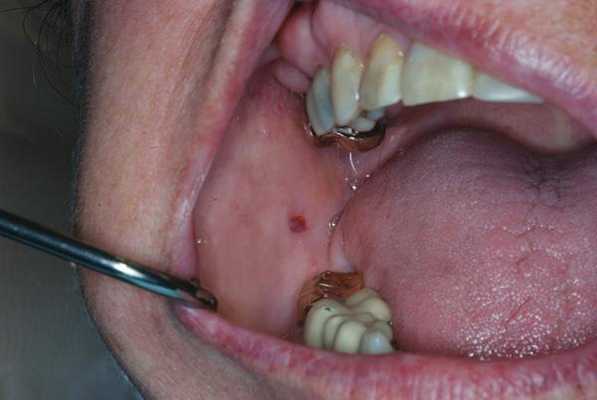

При уменьшенном слюноотделении слизистая оболочка полости рта становиться сухой и в ходе диагностике к ней могут прилипать перчатки, валики и даже стоматологические зеркала. На спине языка могут визуализироваться нитевидные сосочки и трещины, наличие которых позволяет поставить диагноз волосатого языка (фото 1). В пришеечных областях зуба часто визуализируются участки кариозного поражения (фото 2), небольшие эритематозные пятна диагностируются на слизистой щеки, где также могут присутствовать следы накусывания от зубов (фото 3). У пациентов также могут отмечаться признаки гингивита, рецессии и пародонтита (фото 4).

Фото 3. Следы накусывания щеки.

Без надлежащего слюноотделения и в условиях нарушенного уровня рН ротовой полости, ее пространство быстро колонизируется кариесогенными микроорганизмами, которые являются основным патологическим фактором развития поражений твердых тканей зубов. Что же касается связи между ксеростомией и заболеваниями пародонта, то данные литературы в этом плане весьма противоречивы. Некоторые исследователи обнаружили, что пародонтологический статус пациентов с синдромом Шегрена аналогичен таковому у пациентов группы контроля, другие же наоборот – утверждают о худшем состоянии тканей пародонта у пациентов с ксеростомией. Последние аргументируют повышенный риск поражения пародонта увеличенным формированием зубного налета вследствие дефицита слюны. Кроме того, недостаток слюны значительно повышает риск возникновения грибковой инфекции в полости рта, особенно кандидоза, не говоря уже о том, что у большинства пациентов с ксеростомией наблюдаются признаки углового хейлита и атрофия сосочков языка. Будучи сильно связанными с изменениями микрофлоры ротовой полости, такие состояния обуславливаются в первую очередь грибами рода кандида, которые присутствуют в ротовой полости, на коже и в кишечнике. Взаимодействие с белками слюны частично помогает организму контролировать колонизацию грибов рода Candida в полости рта. Микрофлора ротовой полости может изменяться, что приводит к прогрессивному увеличению количества не только оппортунистических, но и патологических бактериальных агентов (фото 2).

Фото 2. Псевдомембранозный кандидозный стоматит у пациента с ксеростомией.